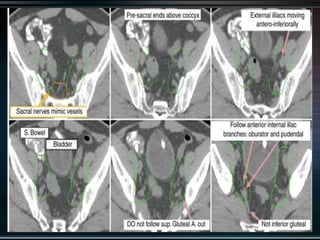

RTOG GU Consensus on pelvic LN CTV volumes:

 Commence contouring the pelvic CTV LN volumes at the L5/ S1

interspace (the level of the distal common iliac and proximal

presacral lymph nodes).

 Place a 7-mm margin around the iliac vessels connecting the

external and internal iliac contours on each slice, carving out

bowel, bladder, and bone.

 Contour presacral lymph nodes from S1 through S3, posterior

border being the anterior sacrum, and anterior border

approximately 10 mm anterior to the anterior sacral bone

carving out bowel, bladder, and bone.

 Stop external iliac CTV lymph node contours at the top of the

femoral heads (bony landmark for the inguinal ligament).

 Stop contours of the obturator CTV lymph nodes at the top of

the symphysis pubis.